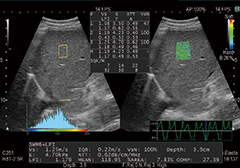

Detective Flow Imaging(DFI)

これまで描出困難であった低流速の血流を表示する新しいイメージング技術です。

独自のアルゴリズムで微細な血流をより高分解能に感度よく描出します。